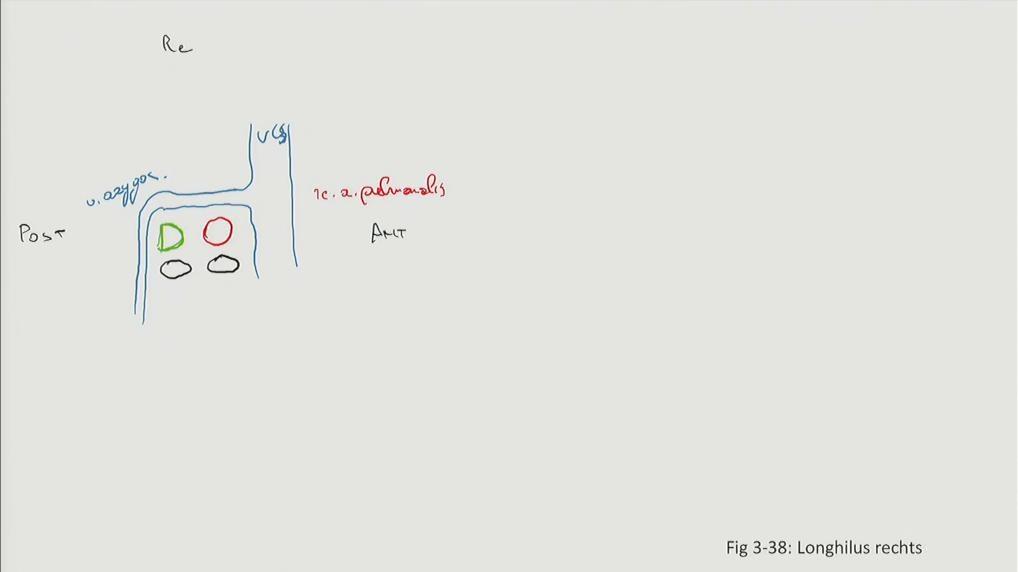

Fig 3.38a: Longhilus rechts

v. cava superior v. azygos a. pulmonalis dextra vv. pulmonales (zwart) bronchus

Grays: Fig 3.45